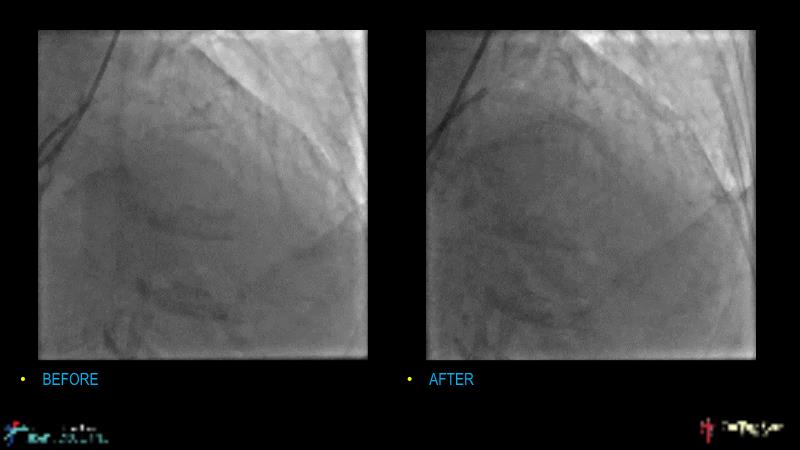

Watch this case-based session to follow discussion about how to choose between DES & DCB, how both can be complementary in diffuse disease as well as in complex PCI, and how physiology and imaging can help guiding PCI, and follow a patient's treatment live.

- To learn the tips and tricks in performing complex PCI intervention with DES and/or DCB

- To discuss cases when DES and DCB are complementary

- To discover strategies to simplify complex PCI cases with the latest DES and DCB